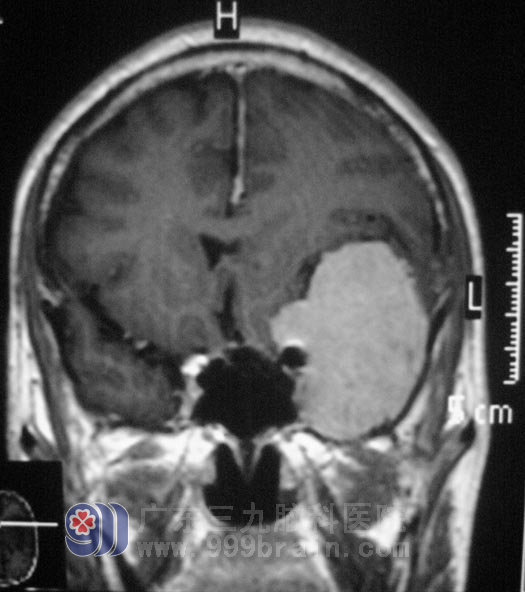

经普通脑电图检查提示轻中度异常脑电图,左侧脑区慢波稍有明显,左额区稍著,头颅MR检查提示:左侧蝶骨嵴占位性病变,左侧大脑镰旁占位性病变,考虑脑膜瘤可能。

完善相关检查后,鲁明主任主刀,行左侧翼点入路蝶骨嵴脑膜瘤切除术+颅内压监护探头置入术,术中可见颞叶处肿瘤血供丰富,肿瘤主要位于硬膜下及颞窝内,包膜完整,基底部位于蝶骨嵴处,大小约4.0cm×4.7cm×5.9cm左右,在显微镜下将肿瘤全切,手术非常顺利。术后老张恢复良好,没有出现异常不适。病理证实为:(蝶骨嵴)纤维型脑膜瘤,WHO I 级。住院九天即满意出院。